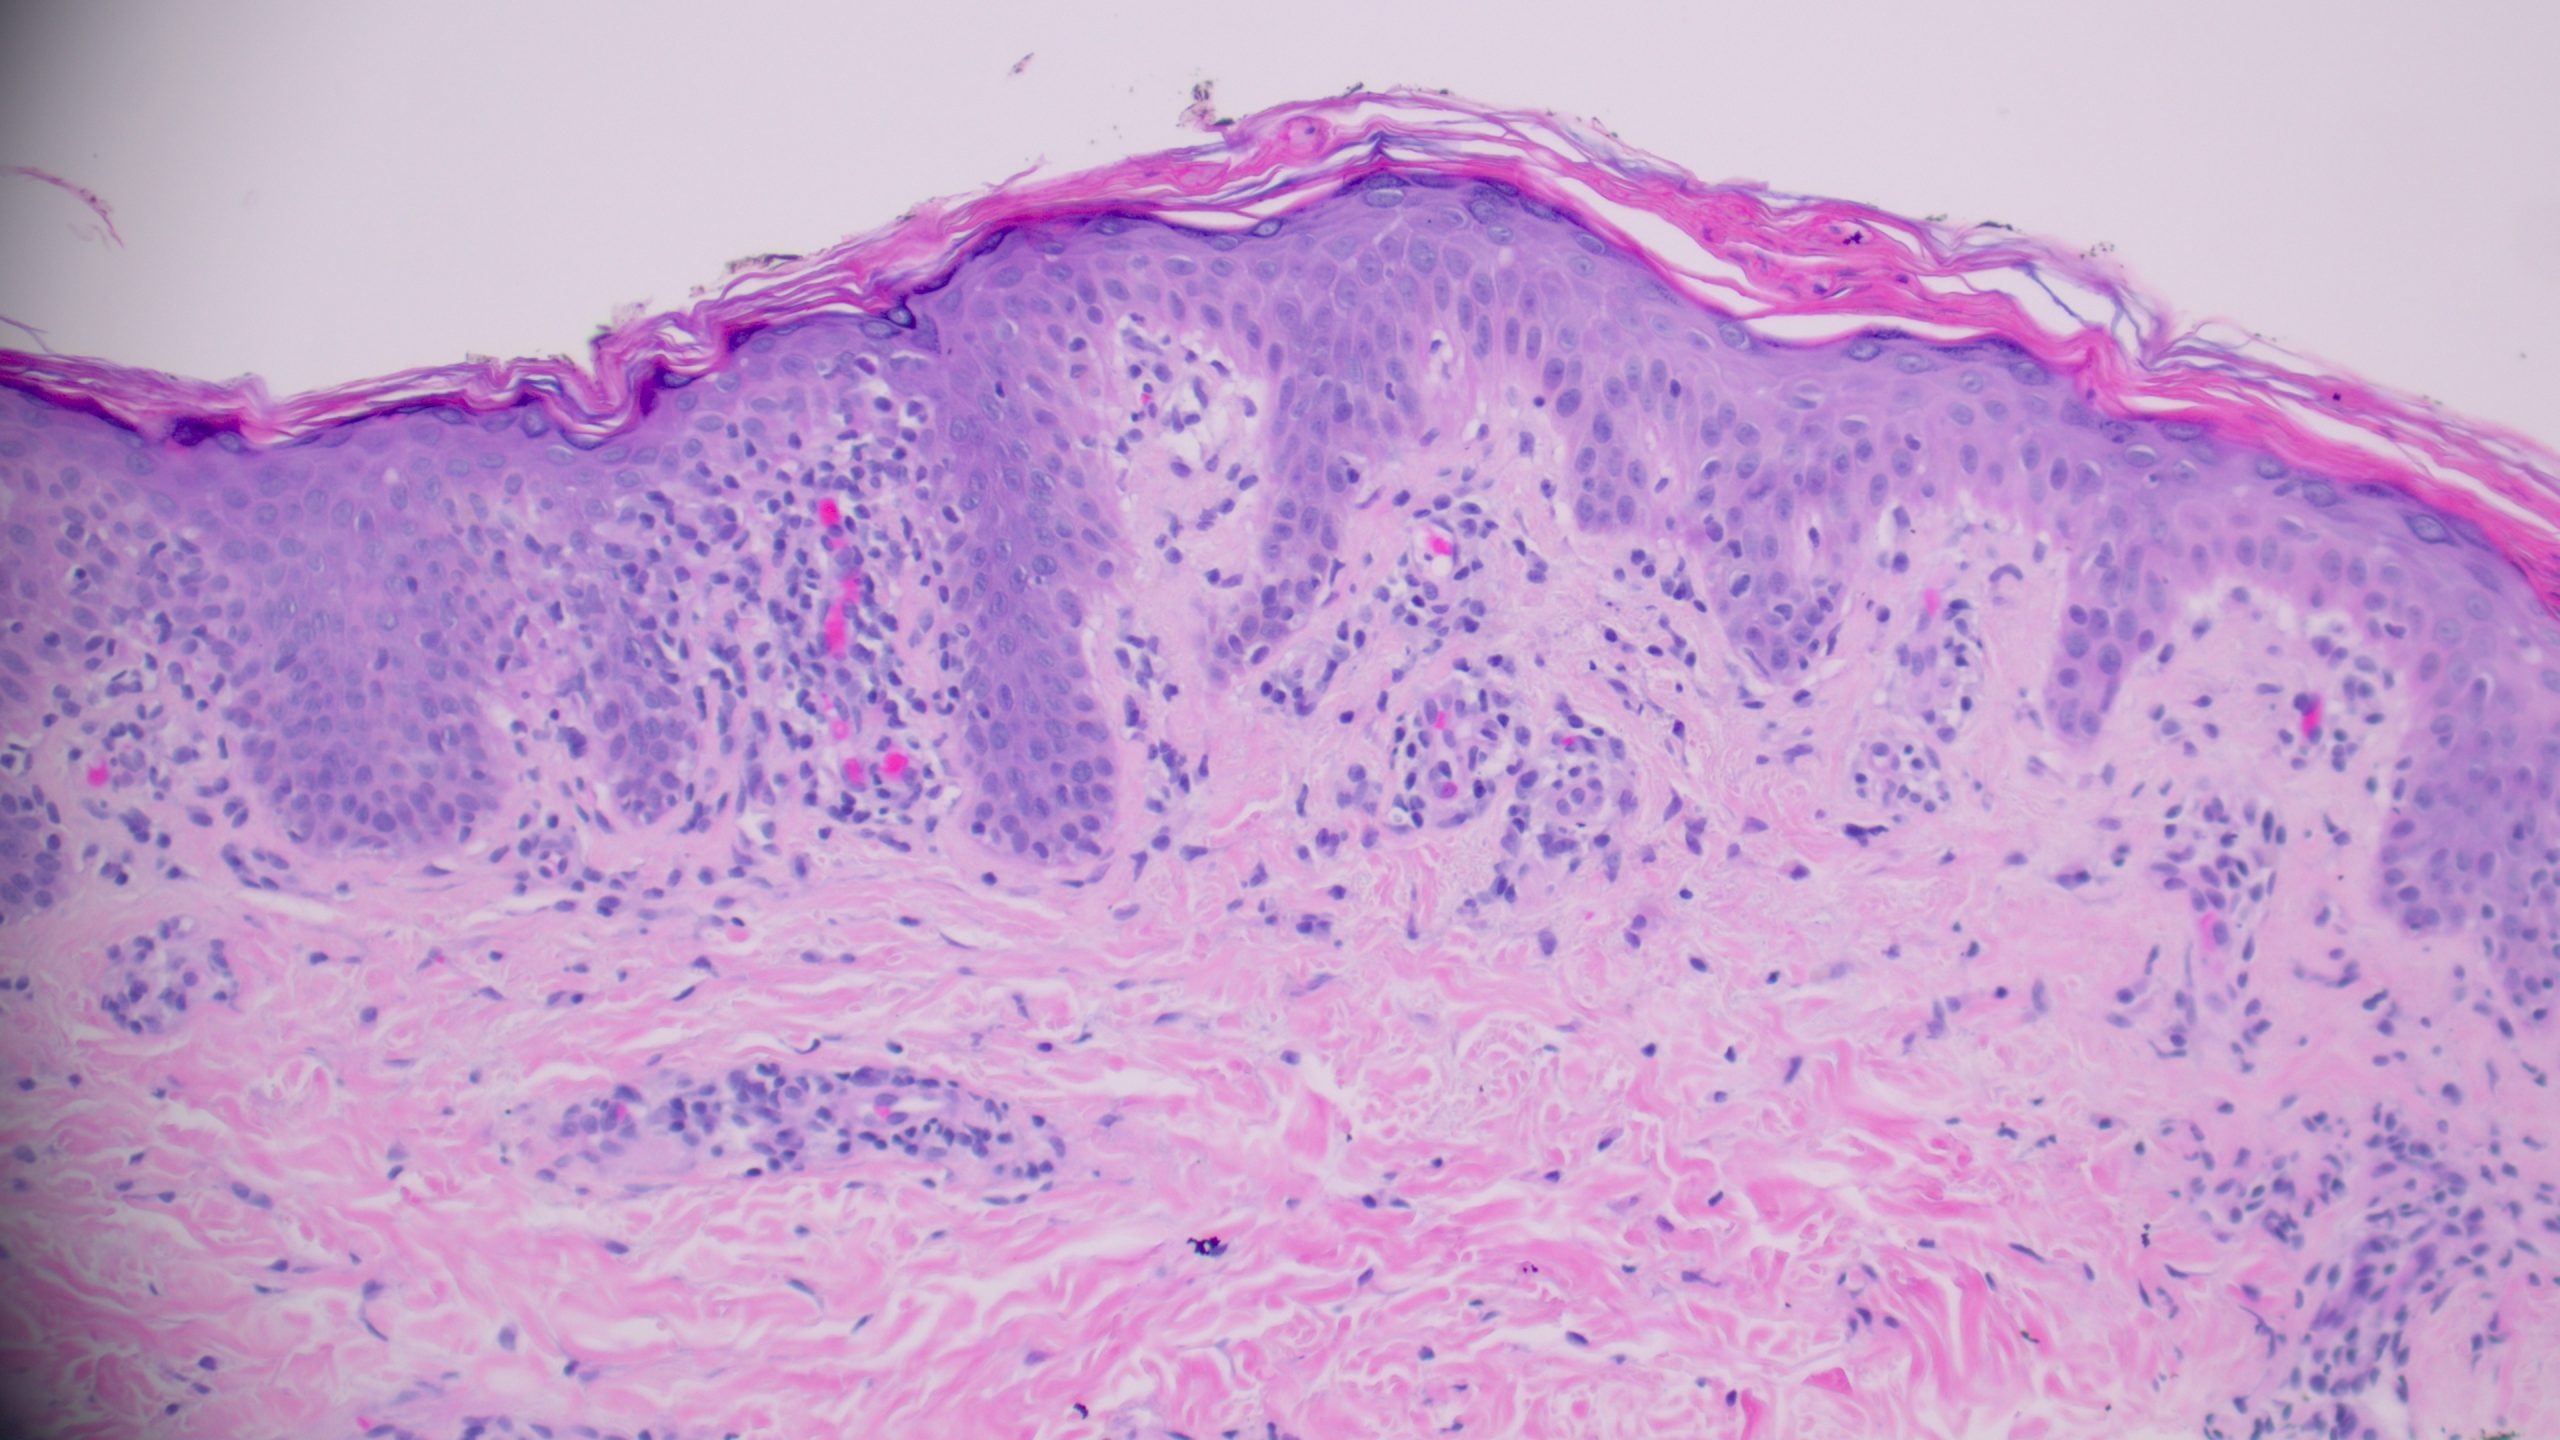

(High power showing necrotic keratinocytes and erythrocyte extravasation into the epidermis)

Pityriasis Lichenoides et Varioliformis Acute (PLEVA)

The combination of a wedge-shaped perivascular lymphocytic infiltrate, necrotic keratinocytes in the epidermis with overlying parakeratosis, and erythrocyte extravasation into the epidermis and superficial dermis is diagnostic of PLEVA. This triad, together with the clinical picture of a young patient with a diffuse papular rash on the trunk, clinches the diagnosis. PLEVA commonly affects patients under 30 years of age, with lesions involving the trunk and proximal extremities presenting as red-brown, mildly pruritic papules that may form blisters, crusts, or ulcers.

PLEVA is a classic dermatopathology “wedge-shaped mimic” that rewards careful microscopic examination at every power level. Remember: the triad of wedge-shaped infiltrate + epidermal necrosis + erythrocyte extravasation tells the story — and immunohistochemistry closes the case when LyP is in the differential.